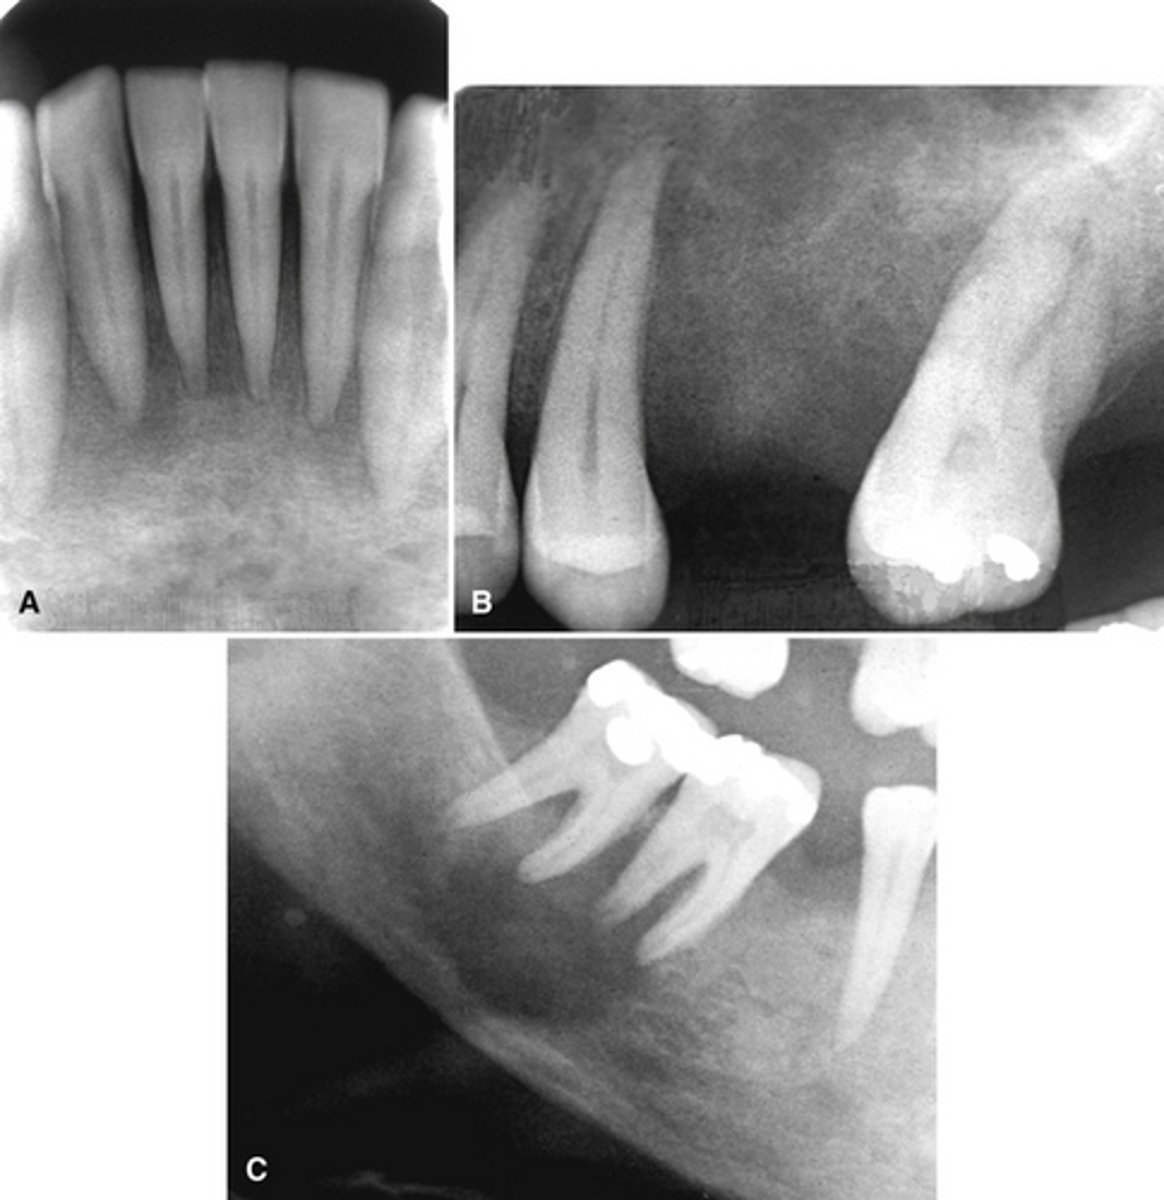

Patient has DJD.

The top images show the subchondral/ Ely cyst, a pseudocyst of connective tissue, granular tissue and osteoid, the bottom images show the same patients left side with broad erosion, a lack of cortication, loss of joint space.

What is the diagnosis of the patient based off these radiographs and what are the features? (Top images = patients right condyle) (bottom images= same patients left condyle)

Patient has DJD, there is significant erosion and loss of joint space.

A and B show prominent osteophyte formation at the anterior aspect

C shows multiple subchondral erosions

What is the diagnosis of the patient based off these radiographs and what are the features?